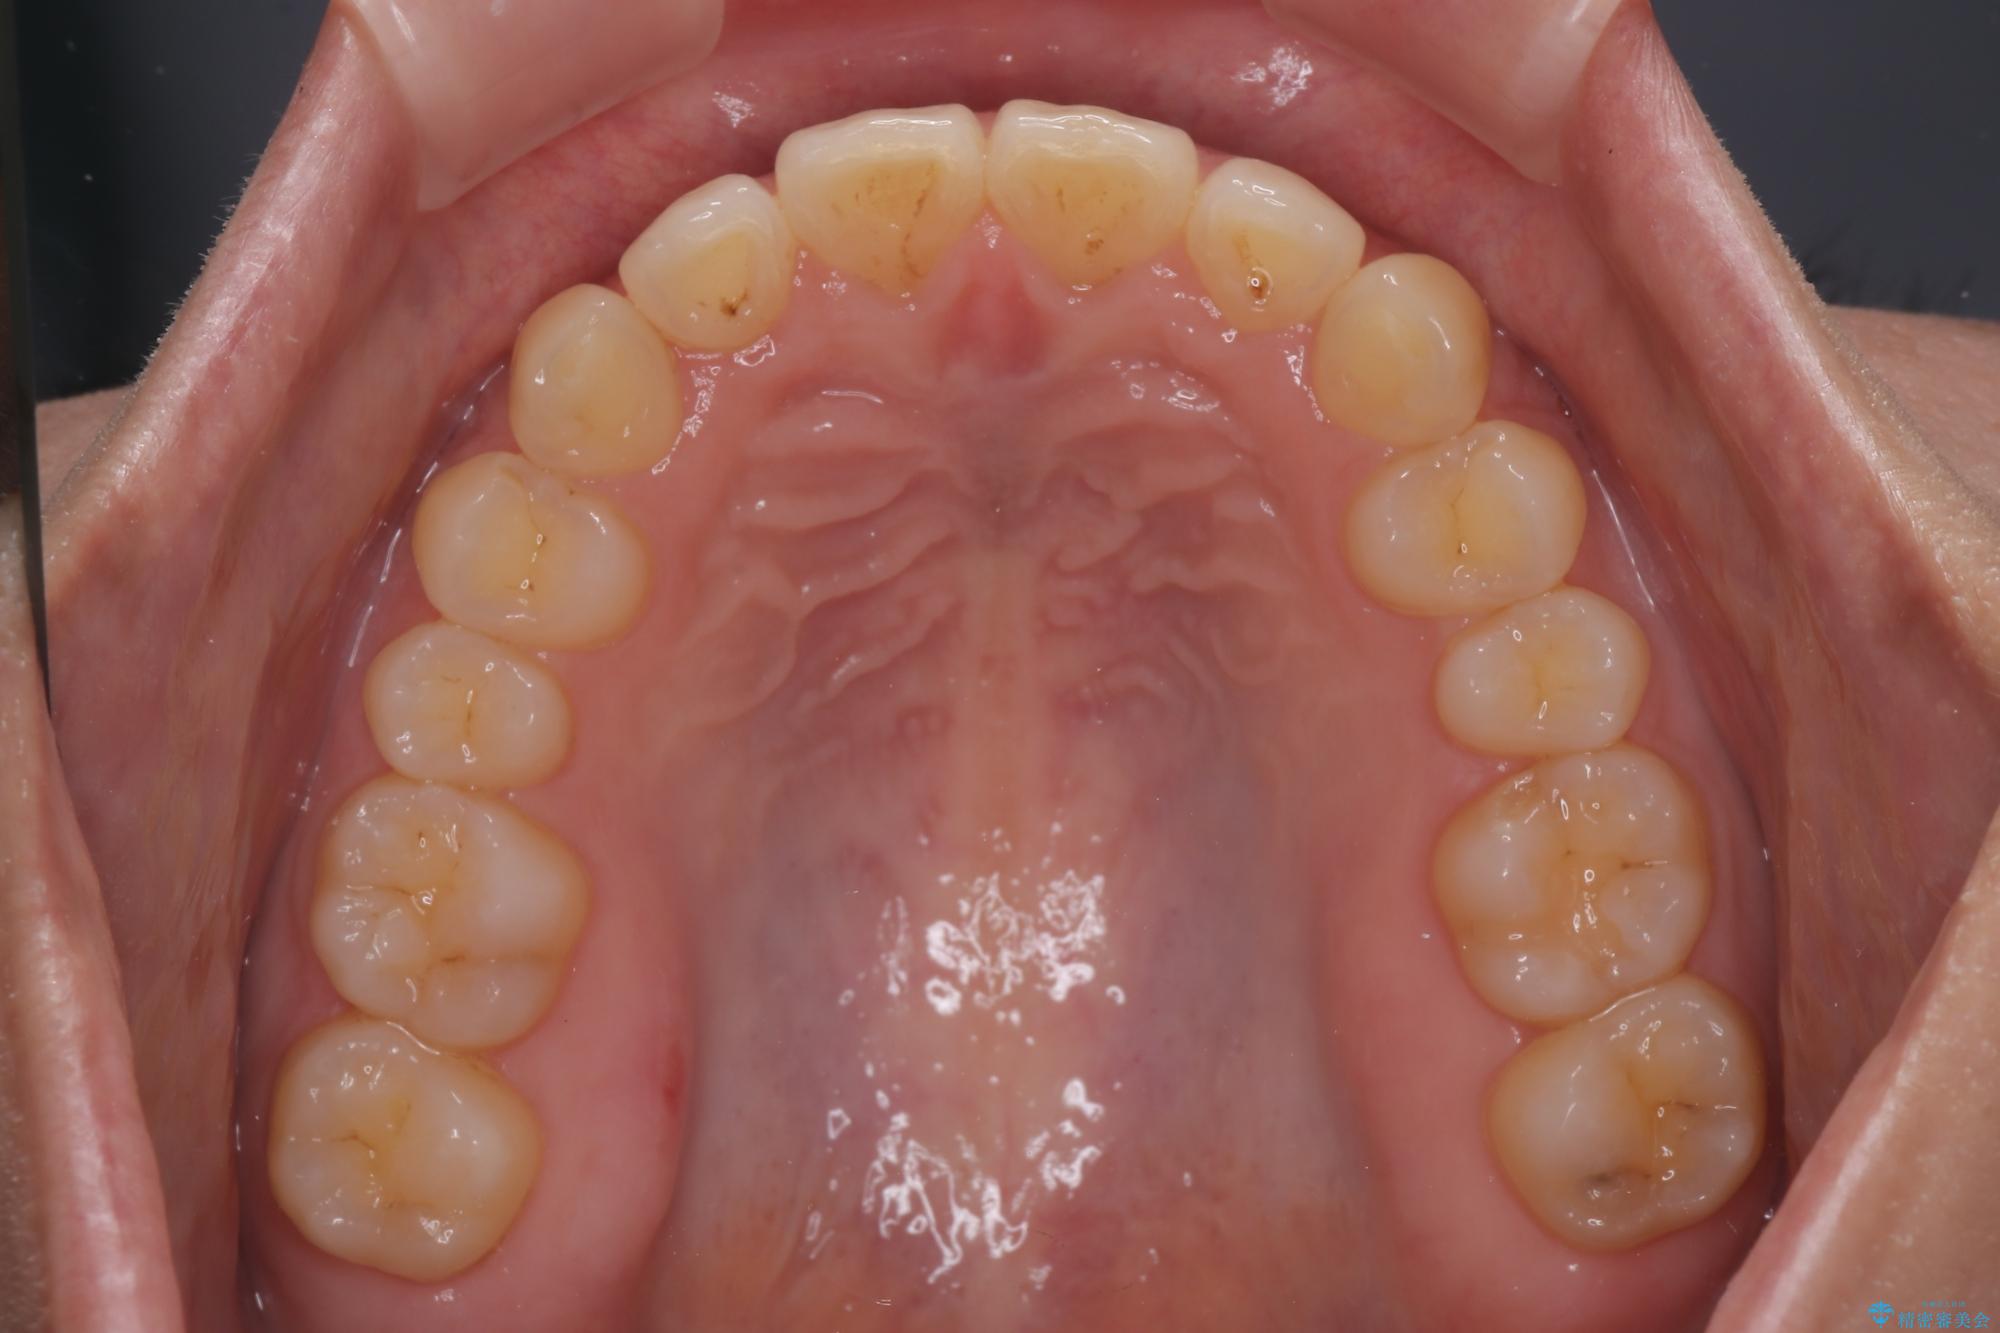

隠れた前歯が気になる ディープバイトのワイヤー矯正治療

下顎臼歯を起き上がらせるためにユーティリティーアーチを使用し、一気に深い咬み合わせを改善することができました。